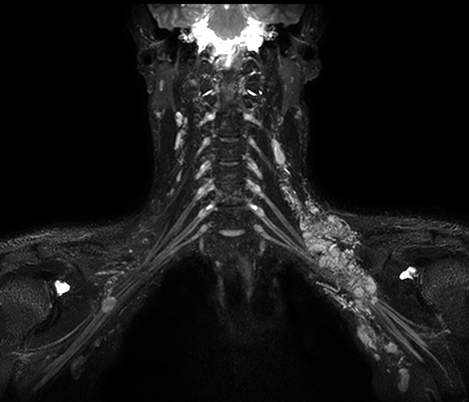

El 70% de los radiólogos consideran que las indicaciones neurológicas son un desafío, sobre todo debido a la falta de técnicas apropiadas de imagenología y visualización¹. Philips tiene como objetivo proporcionar la mejor claridad de diagnóstico posible y orientación terapéutica para todos los pacientes con trastornos neurológicos. Al aprovechar nuestra plataforma digital dStream, este año presentamos un conjunto de estrategias nuevas de imagenología y visualización. Esto puede ayudarlo a resolver preguntas sobre neurología complejas con mayor certeza, así como a desbloquear nuevos territorios neurológicos en aplicaciones neurofuncionales avanzadas. Este es un paso clave para aumentar el diagnóstico neurológico y, en última instancia, impactar más vidas con la RM. ¹ TMTG Market Survey 2016